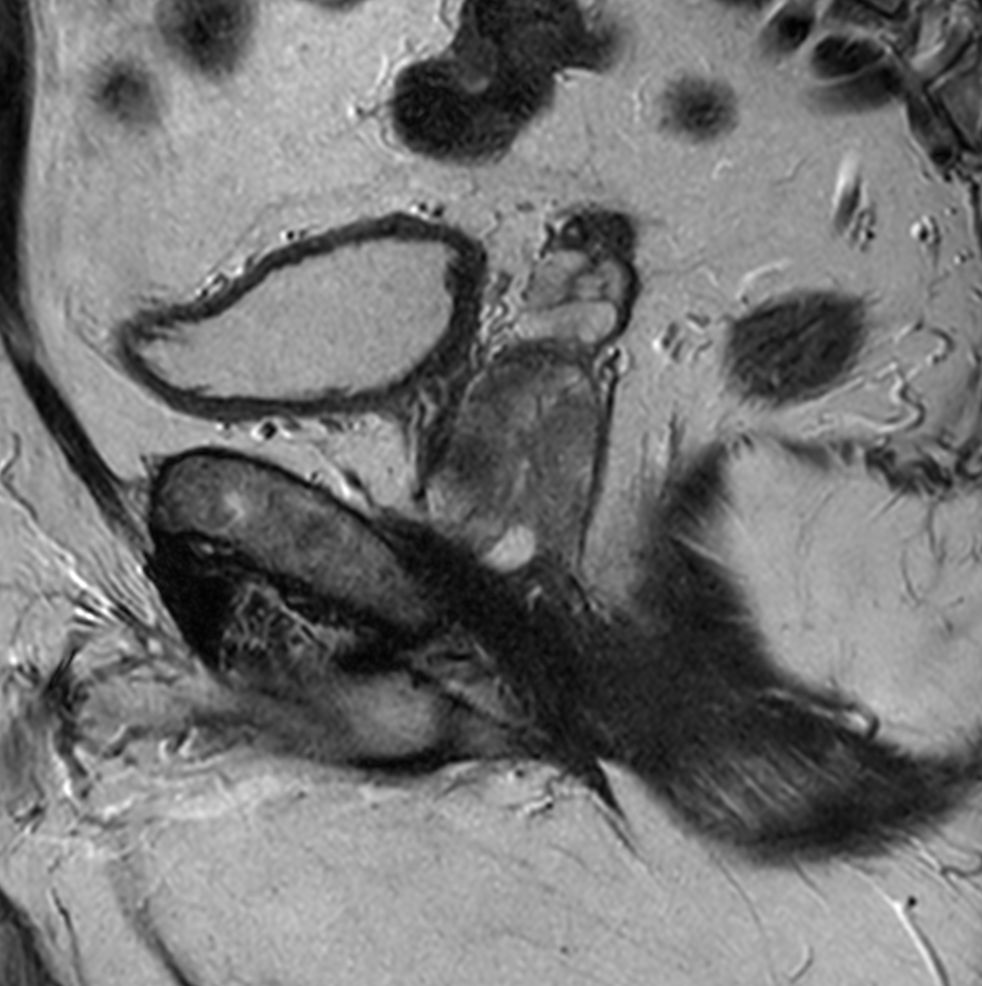

Axial T2w TSE

Axial 3D T2w TSE (PelvisVIEW)

Coronal T2w TSE

Sagittal T2w TSE

Sagittal T2w TSE MultiVane XD